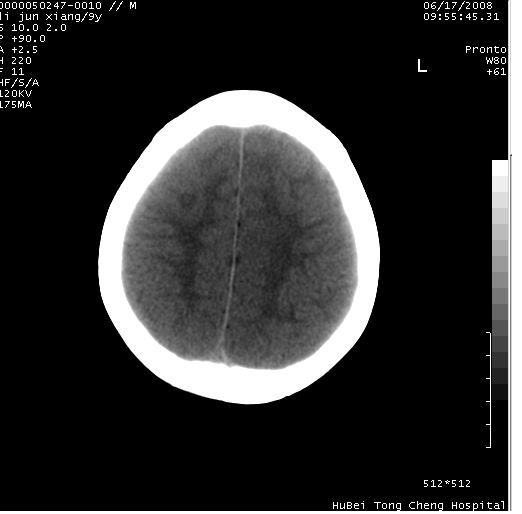

颅脑ct轴位平扫(层厚、层距均为10mm),图像如下:

调骨窗:颅骨未见明确异常。

只是双侧脑室不对称,其它未见异常啊